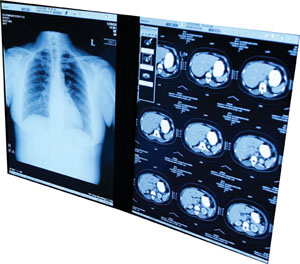

CT Scan ImageCancer and Tobacco

The facts about the health risks of cancer and smoking.